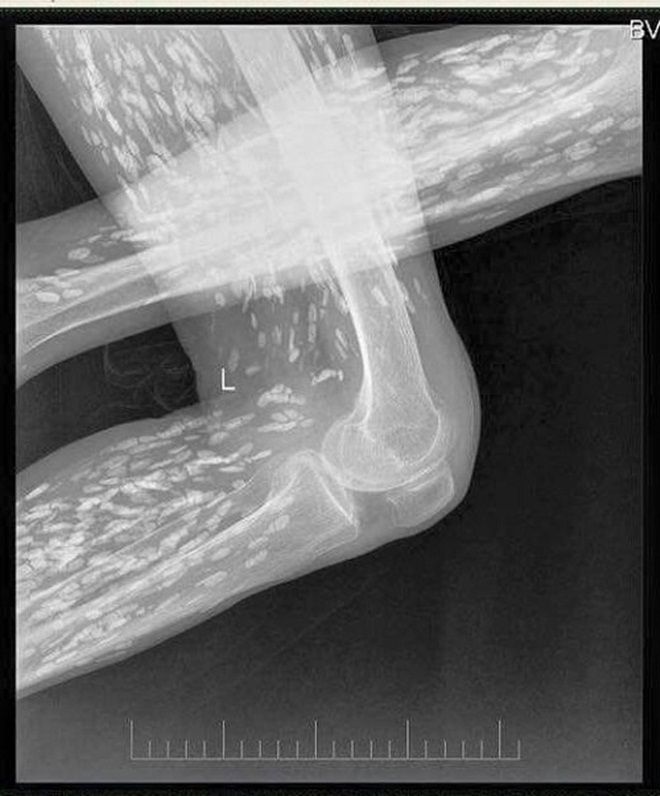

Trong những ngày qua, trên mạng xã hội chia sẻ rất rầm rộ về một hình ảnh chụp Xquang, kèm theo hình ảnh này là lời cảnh báo: “Hình ảnh được ghi nhận tại Bệnh viện đa khoa Trung ương Thái Nguyên.

Người gạo là có thật các bác ạ. Hình ảnh XQ trên là của bệnh nhân nhiễm sán xơ mít do ăn phải thức ăn sống (có thể là rau sống, tiết canh, gỏi cá…) có nhiễm trứng, ấu trùng sán…”.

Rất nhiều người khi quan sát hình ảnh này không khỏi hốt hoảng khi hình những nốt trắng được cho là sán sơ mít có ở khắp cơ thể. Thậm chí, có người còn bình luận: “Người nhiều sán thế này, có khi đứt tay máu không chảy mà sán lại chạy ra”.

Để có thông tin rõ hơn về mặt chuyên môn, chúng tôi đã chuyển hình ảnh này đến BS Trần Huy Thọ - Trưởng khoa Điều trị (Viện Sốt rét - Ký sinh trùng - Côn trùng Trung ương), thì được biết, viện cũng đã gặp nhiều trường hợp bị sán cơ, tuy nhiên nhìn hình ảnh như trên phim thì bản thân bác sĩ Thọ chưa gặp bao giờ.

“Nhiều khả năng đây là sán cơ, tuy nhiên để khẳng định chính xác thì tôi phải hỏi bệnh sử, có hồ sơ bệnh án, kết quả làm các xét nghiệm, thậm chí là cả địa phương nơi đó tập quán ăn uống như thế nào, nếu chỉ nhìn vào hình ảnh thì không thể khẳng định 100%”, BS Thọ cho hay.

Theo bác sĩ Thọ, trong trường hợp sán cơ nhiều như vậy, thì đó có thể là những nốt vôi hóa ở trong cơ. “Đây có thể là những nốt vôi hoá trong cơ, khi nang sán trong cơ thoái triển và thành vôi hoá”, BS Thọ cho biết.